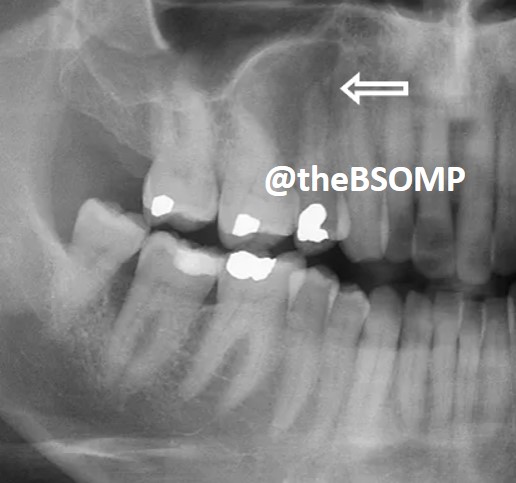

@theBSOMP Case of the Month for Jan/Feb 2024 is now live.

Visit bsomp.org.uk/cotm for details.

Case credit-@histopathhannah @M0llieclark